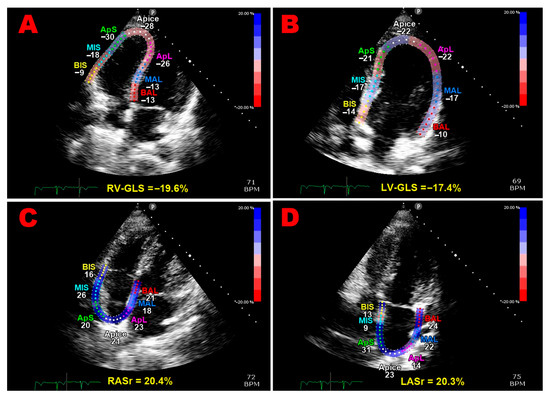

Multipanel Figure 1 illustrates examples of biventricular and biatrial longitudinal strain parameters measured from the apical four-chamber view in a pHDP woman included in the present study.

Figure 1. Illustrations of right ventricular global longitudinal strain (A), left ventricular global longitudinal strain (B), right atrial reservoir strain (C), and left atrial reservoir strain (D) measurements obtained from the apical four-chamber view in a pHDP patient from this study. All myocardial strain values are decreased relative to the established reference ranges. GLS, global longitudinal strain; LASr, left atrial reservoir strain; LV, left ventricular; pHDP, previous hypertensive disorder of pregnancy; RASr, right atrial reservoir strain; RV, right ventricular.